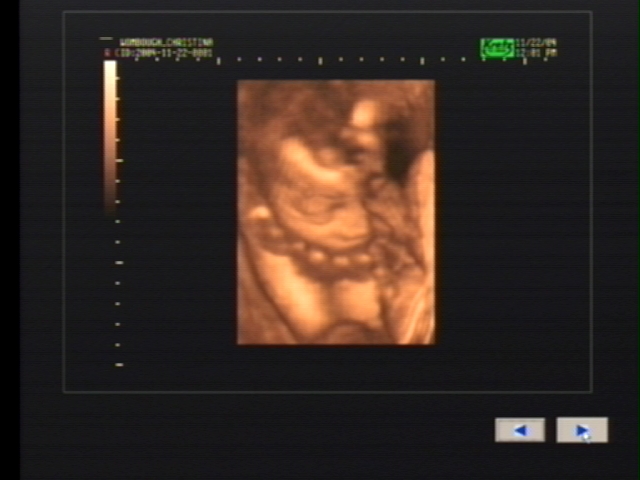

3D Sonogram Pictures

Click on a picture to make it bigger!